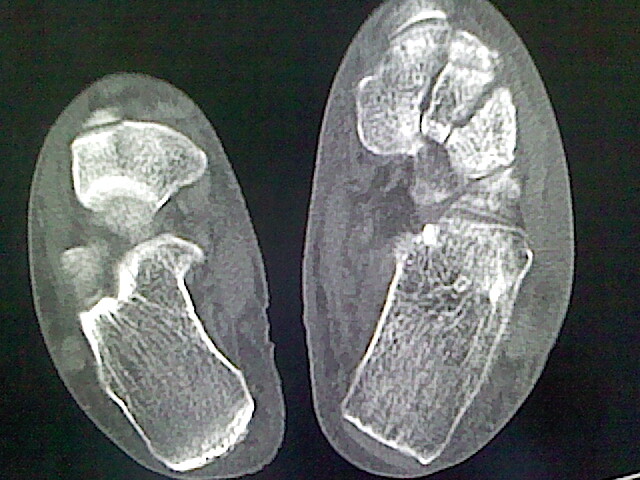

标题: CT16814:男,76岁,左小腿疼痛,不能站立 大家给看看 [打印本页]

男,76岁,左小腿疼痛,不能站立

本例骨质改变主要表现为滑膜或韧带区的骨侵蚀融解(胫腓联合区骨质破坏无硬化边),距骨后部骨质破坏区有硬化边及死骨样改变.所以,本例考虑关节结核可能性大,绒毛膜结节性滑膜炎多发于中年,且极少见于膝髋以外的关节,骨质硬坏也以压陷吸收为主,有明显的硬化边,骨膜增生呈结节状(可以mr鉴别),所以本例暂除外.

另不除外可引起相似表现的其他炎症如布氏杆菌性关节炎等